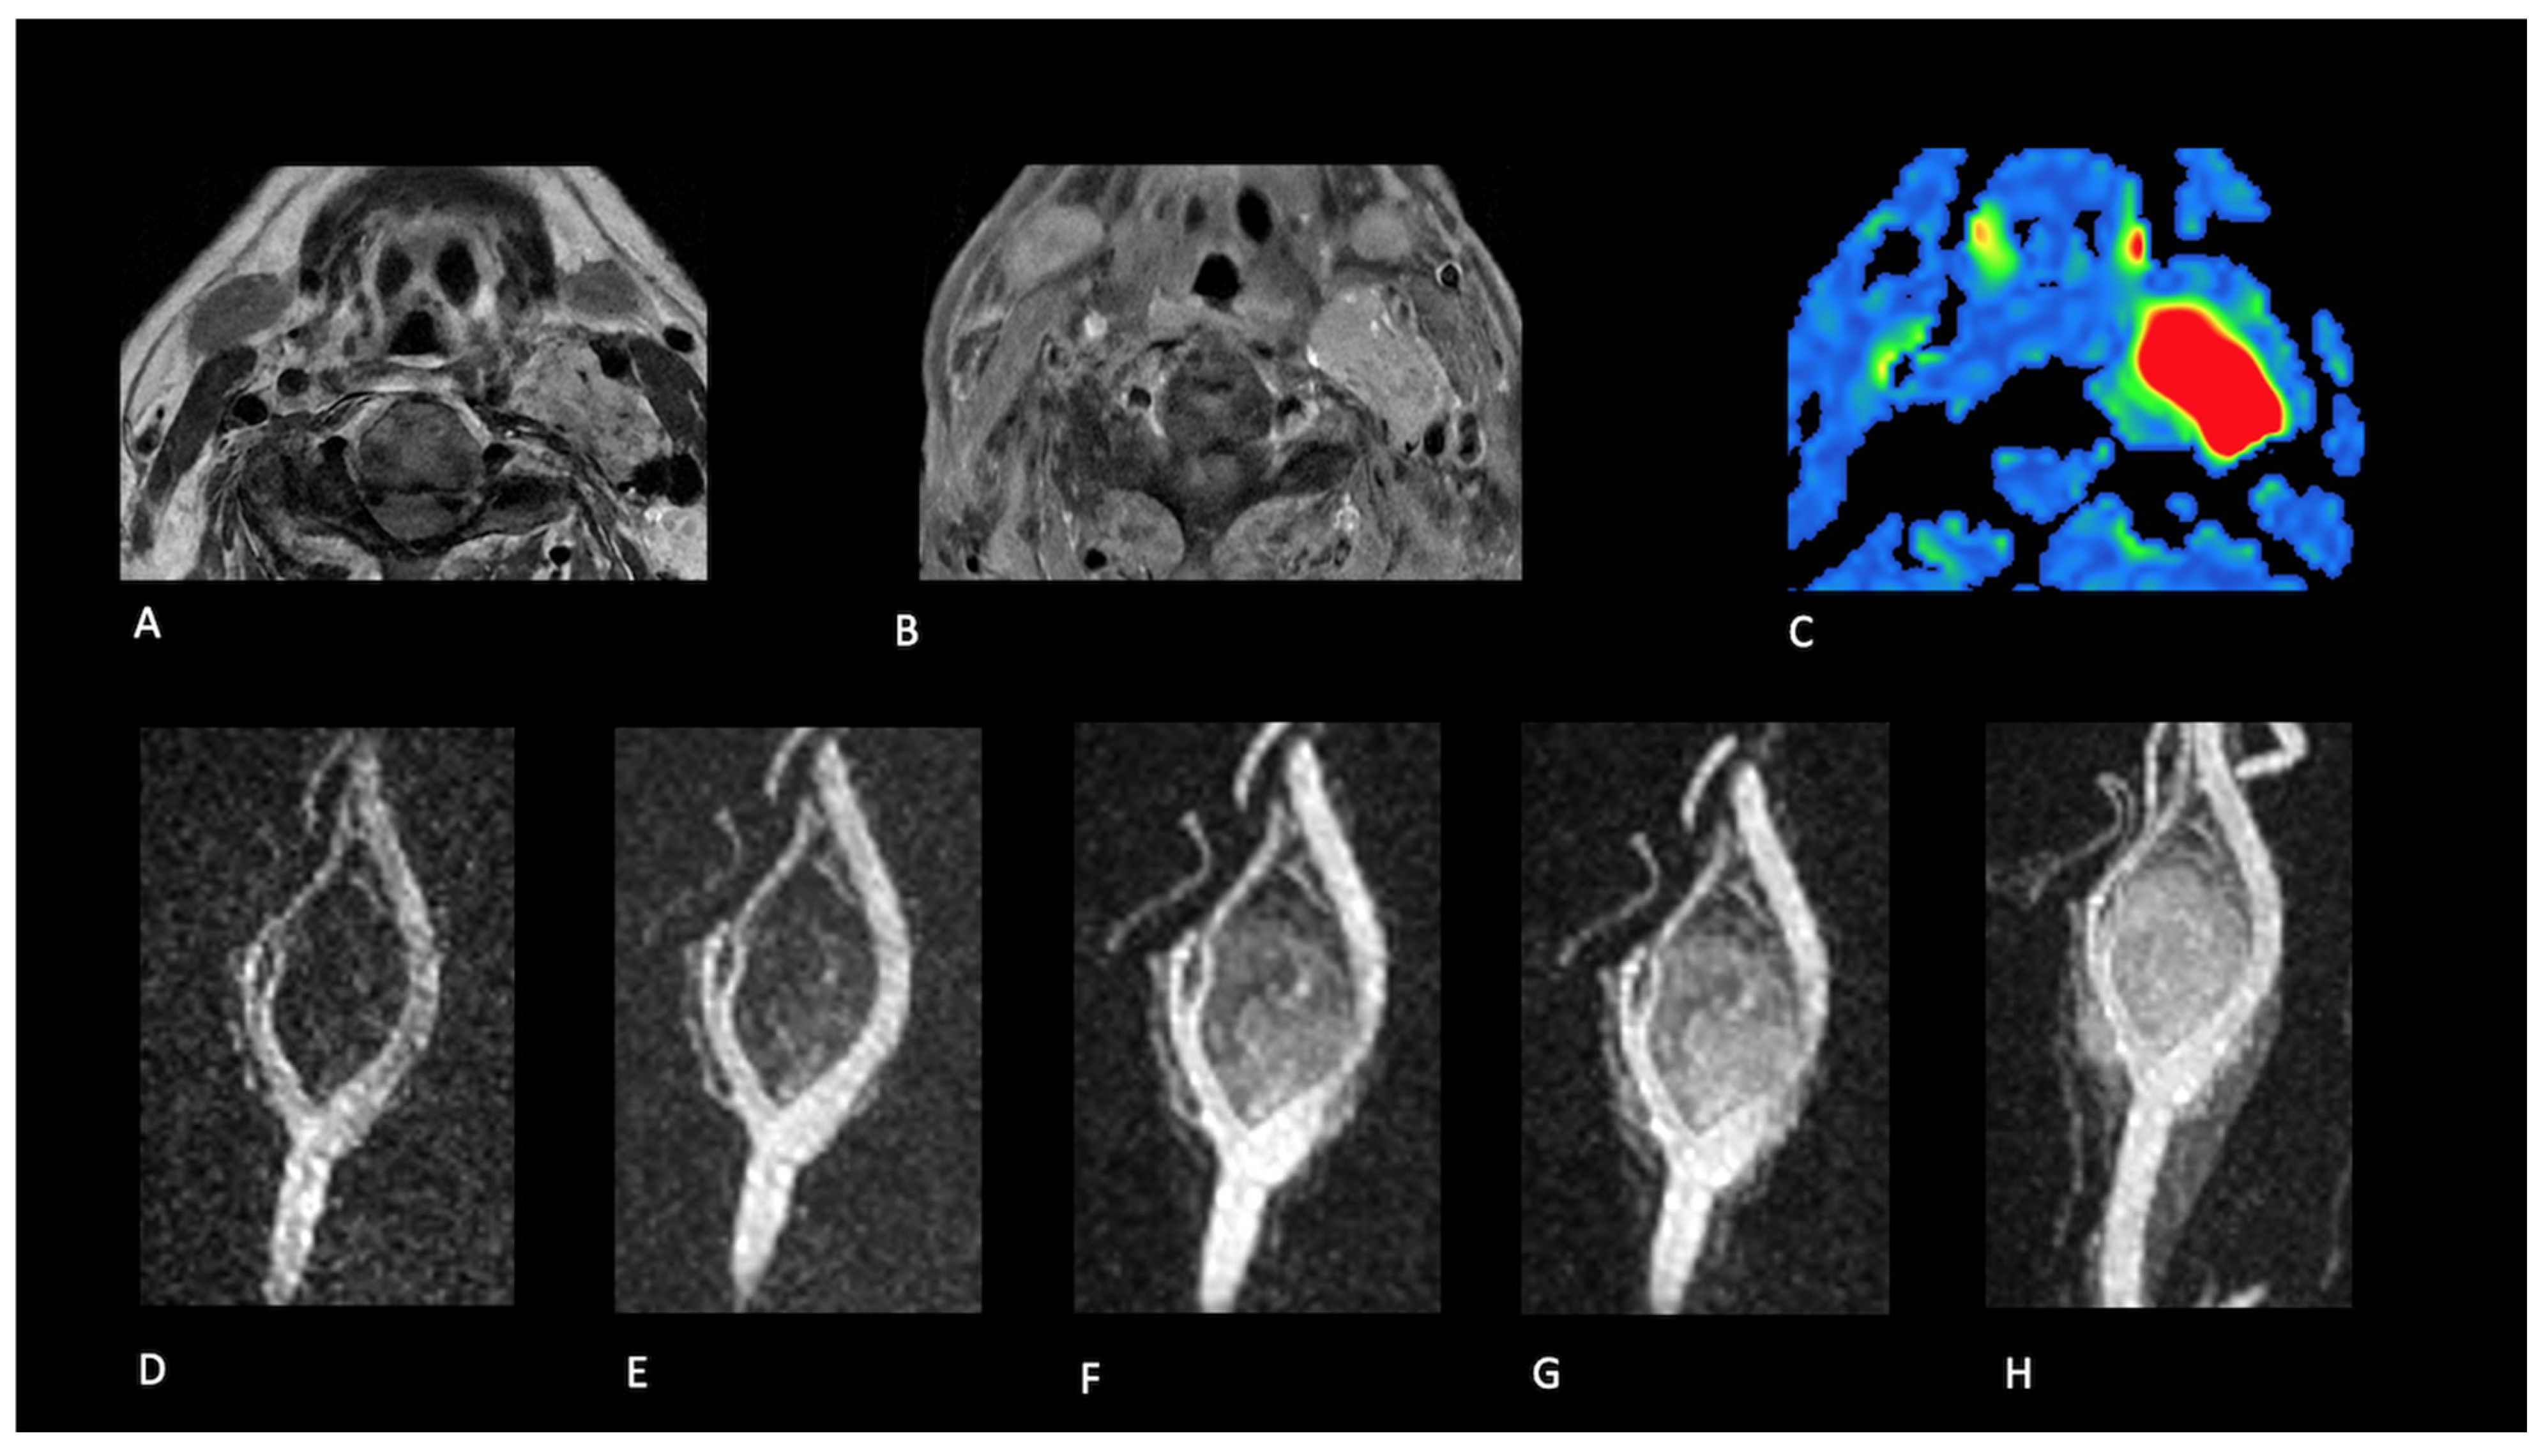

- Presence (present | indeterminate | absent) and site of a lesion.

- Sequence(s) providing greatest diagnostic confidence in detecting/localising NPGLs:

- Single sequences—FS-T2, CE-FS-T1, pcASL, and TRICKS;

- Combined sequences—FS-T2 + CE-FS-T1, and pcASL + TRICKS.